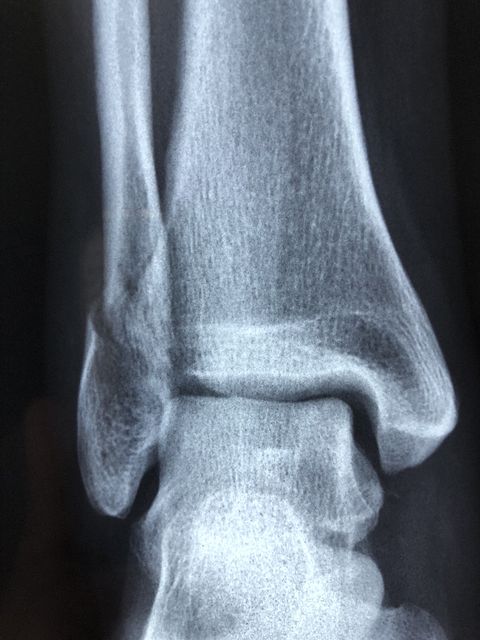

4. Ankle

It is enough only to make a wrong step and to stretch your ankle, or even to break it. Still, being one of the easiest bones to break safely and painlessly, it would probably be a pain in the ass having the cast and not being able to walk normally for the time the ankle needs to heal.